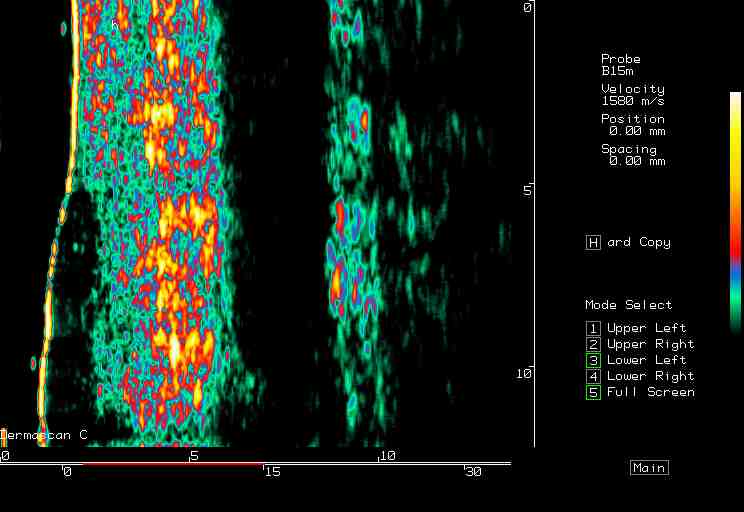

20 MHz 2D images

| Pressure wounds |  Pressure wound, edge |

Pressure wound, open |